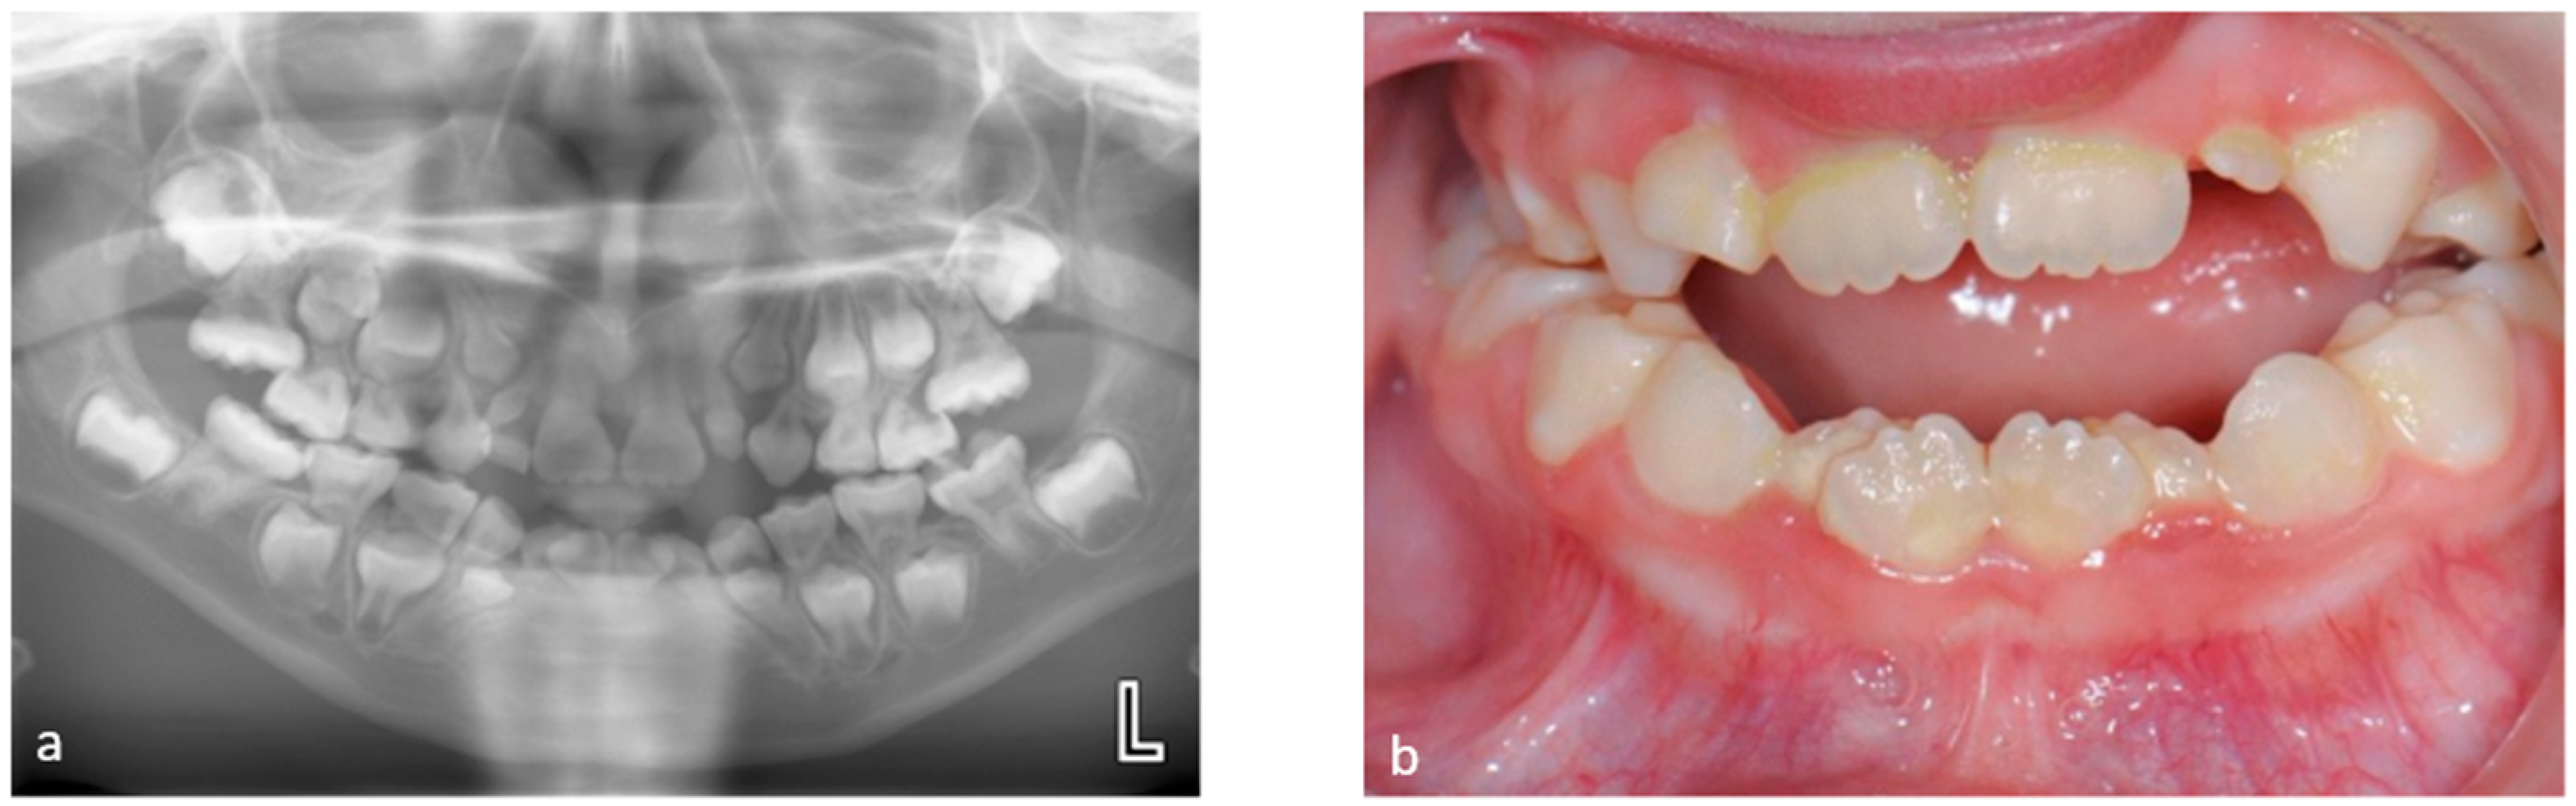

3.1. Tooth Development Disturbances